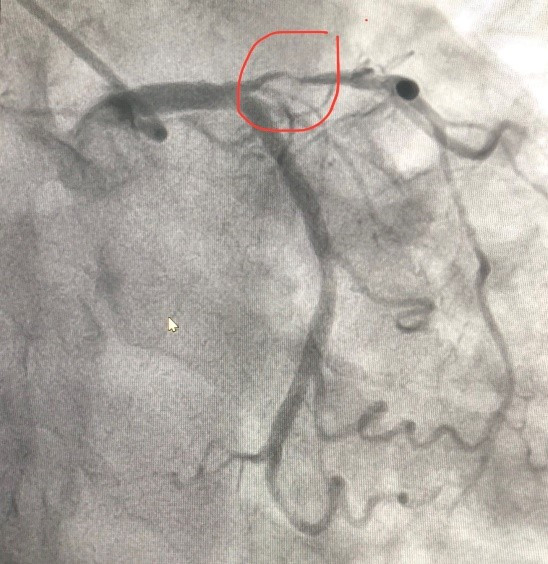

Sau xử trí cấp cứu huyết áp của người bệnh đã tăng lên 110/70mmHg, nhịp tim ổn hơn, được chuyển vào phòng can thiệp Khoa Can thiệp Tim và Mạch máu để tiến hành chụp động mạch vành qua da, kết quả cho thấy hẹp gần tắc đoạn gần động mạch liên thất trước. Kíp can thiệp đã nong bóng và đặt 1 stent phủ thuốc vào vị trí tổn thương.

![]() |

| (Hình ảnh: Hẹp gần tắc động mạch vành trước can thiệp) |